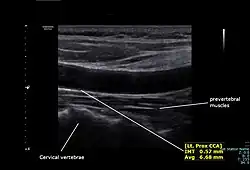

The condition and health of the common carotid arteries is usually evaluated using Doppler ultrasound, CT angiography or phase contrast magnetic resonance imaging (PC-MRI).

Typically, blood flow velocities in the common carotid artery are measured as peak systolic velocity (PSV) and end diastolic velocity (EDV).

In a study of normative men aged 20–29 years, the average PSV was 115 cm/sec and EDV was 32 cm/sec. In men 80 years and older, the average PSV was 88 cm/sec and EDV was 17 cm/sec.[7]